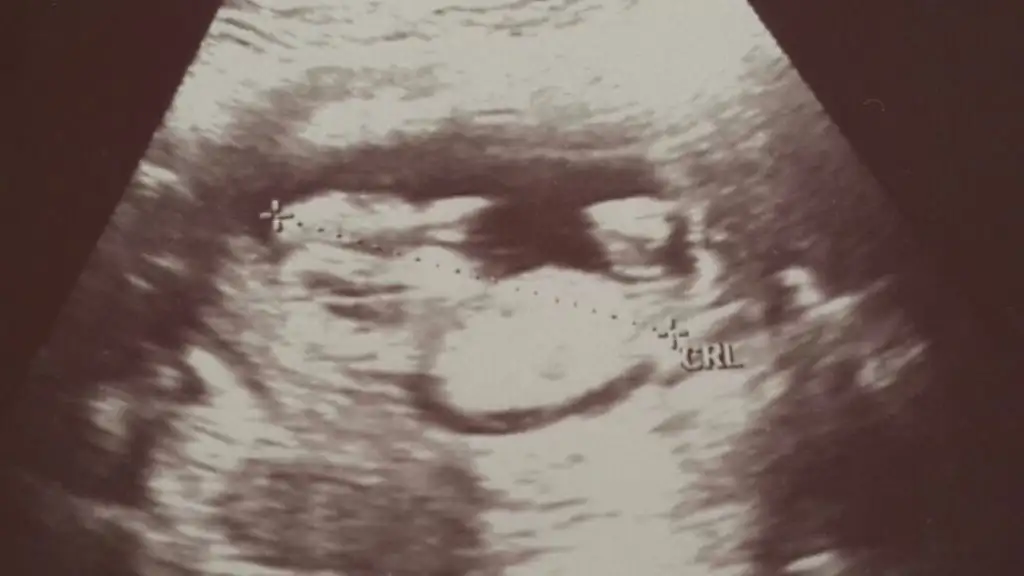

sanki umrumda bana yorum yapmışmıydın önceden buda benim 12 haftalık olan bebişim .bakarmısın benim içinde.

Canım kıza biraz daha fazla benziyor. Ama görüntü kalitesi çok iyi değil. Yanılma Payı ile kız diyorum :)